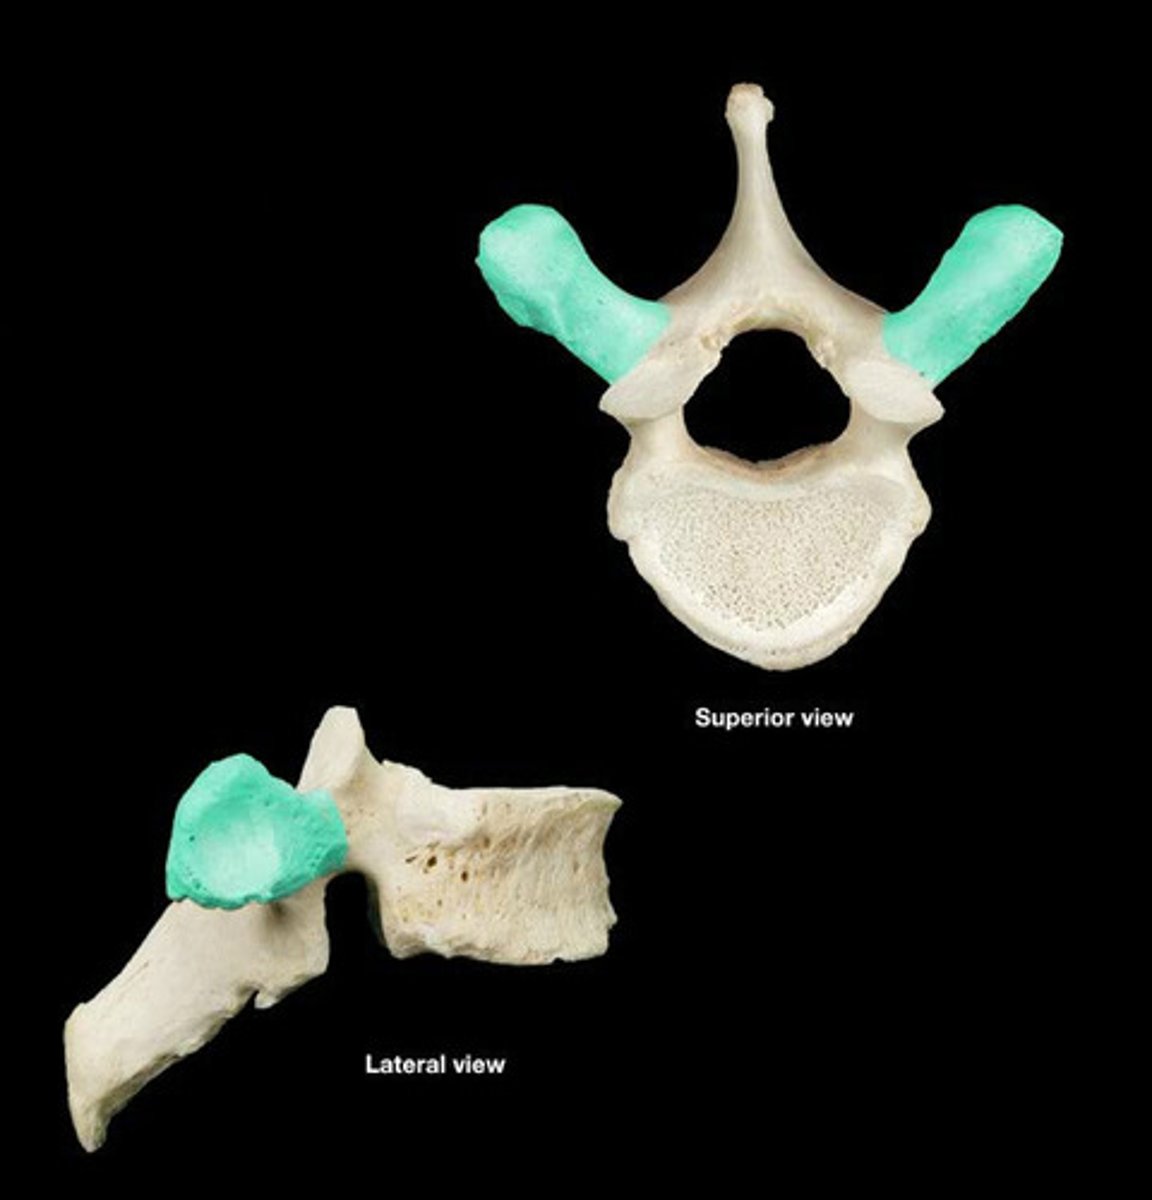

Transverse Process

Superior Articular Facets

Lumbar Vertebrae 5

Vertebral Body

Superior Articular Facets

Inferior Articular Facet